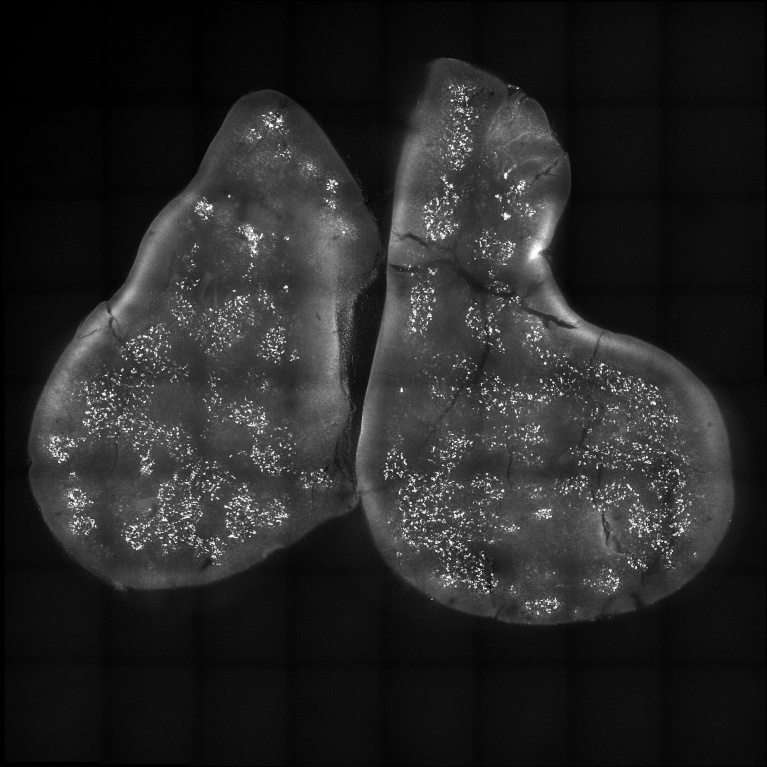

This is a microscopic image of an entire thymus. The thymus is stained for a new type of cell that we discovered called the thymic microfold cell, using a protein marker called GP2. The bright white dots in the image are the microfold cells.

We wanted to understand their distribution in the thymus. As you can see in the image, it is clustered throughout central regions of the thymus called the thymic medulla.